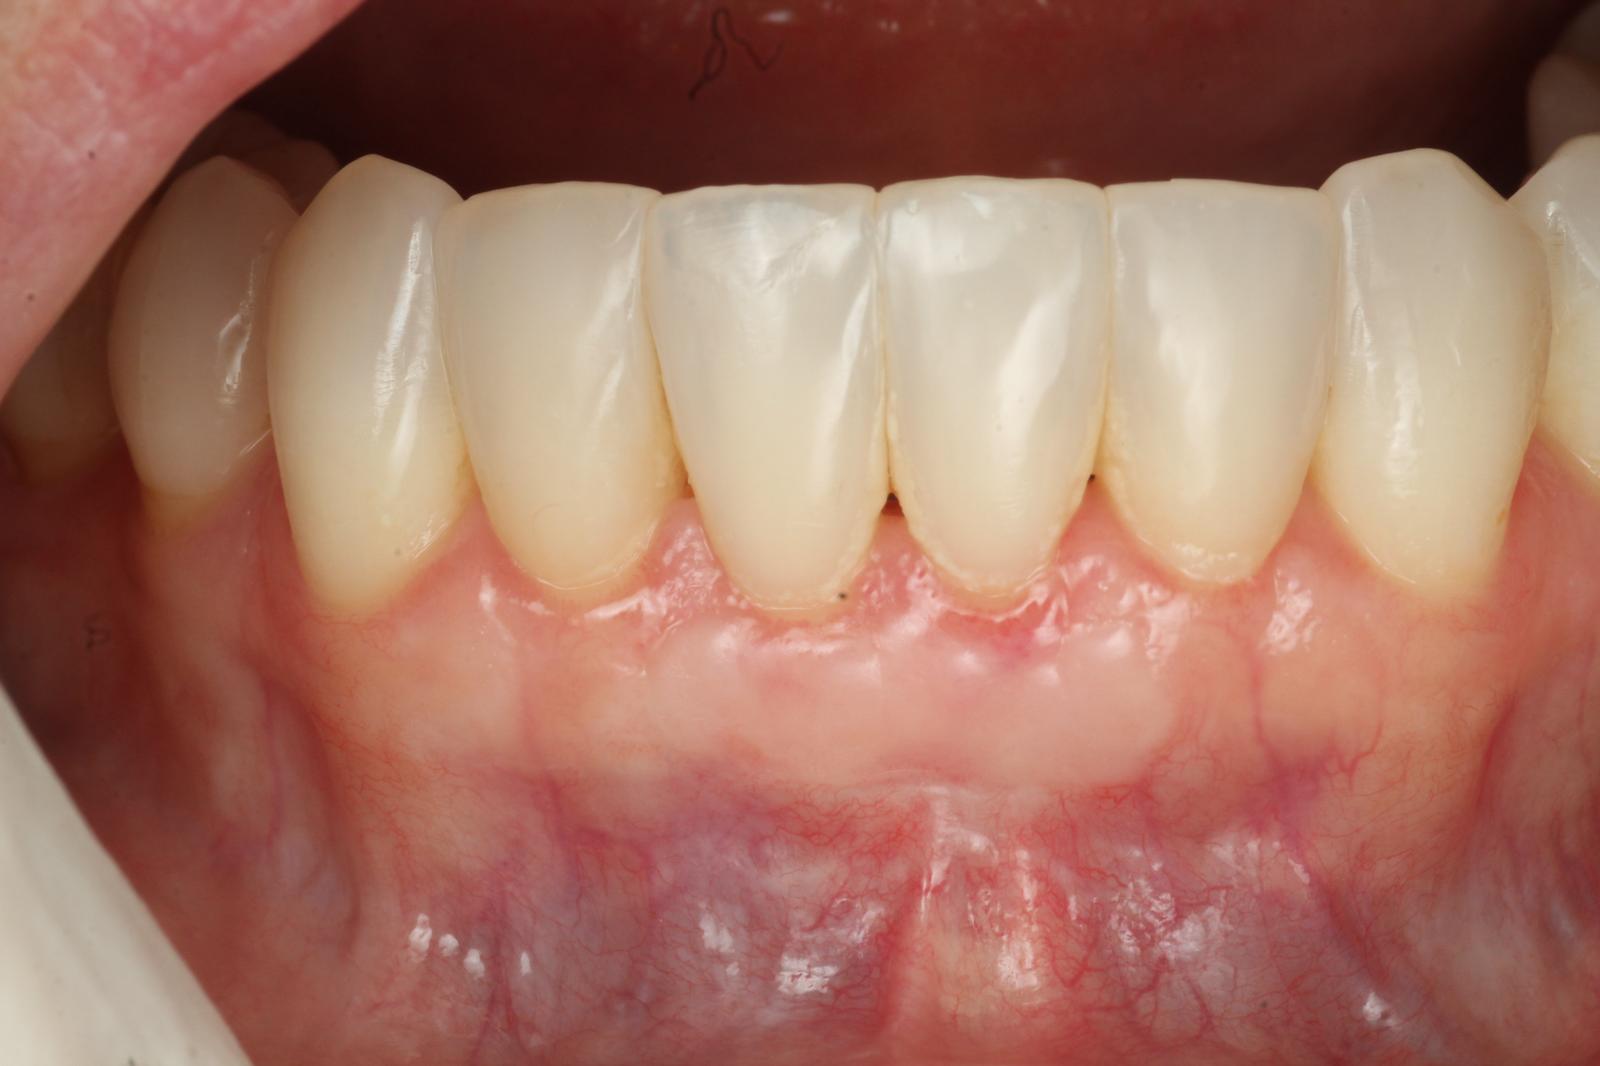

2.Gum Graft Surgery

In cases of gum recession, a gum graft can help restore protective tissue around the teeth. Tissue—often from the roof of your mouth—is grafted onto the affected areas, helping to reduce sensitivity, improve appearance, and prevent further recession.

For severe cases, surgical treatments such as flap surgery, bone grafts, or regenerative procedures may be recommended to restore gum and bone health.